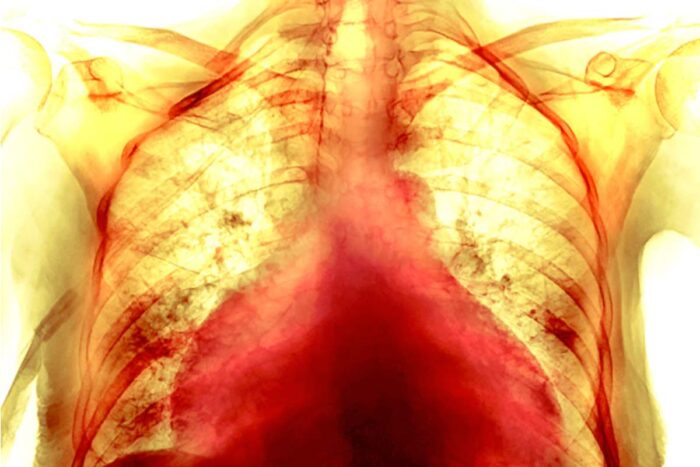

How COVID-19 harms the heart

Colored chest x-ray of the enlarged heart of a 74-year-old female COVID-19 patientP. MARAZZI/SCIENCE SOURCE